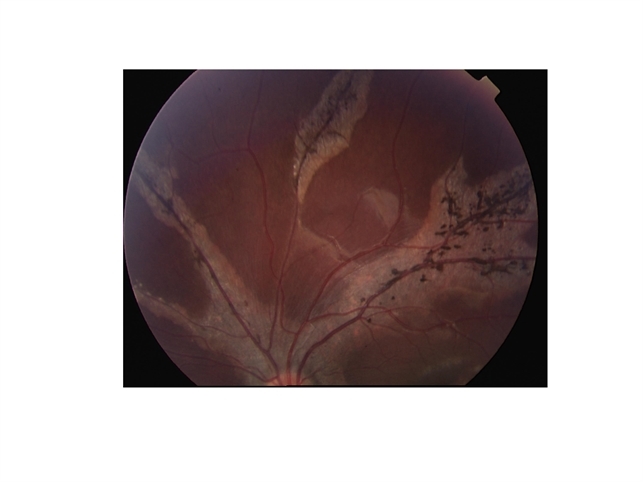

- choroidal atrophy

- 14-year-old black female with Marfan Syndrome.